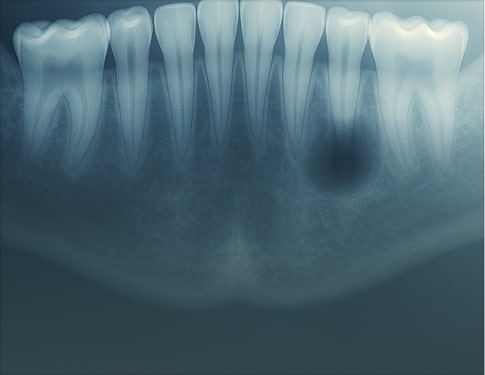

Screening Report is a concise, text-only summary designed for straightforward cases or when you simply need to rule out pathology. This option is often used when an image was taken for a specific purpose, but you’d like a radiologist to review the entire scan as part of our dental teleradiology services, confirming there are no incidental findings across the full set of medical images.